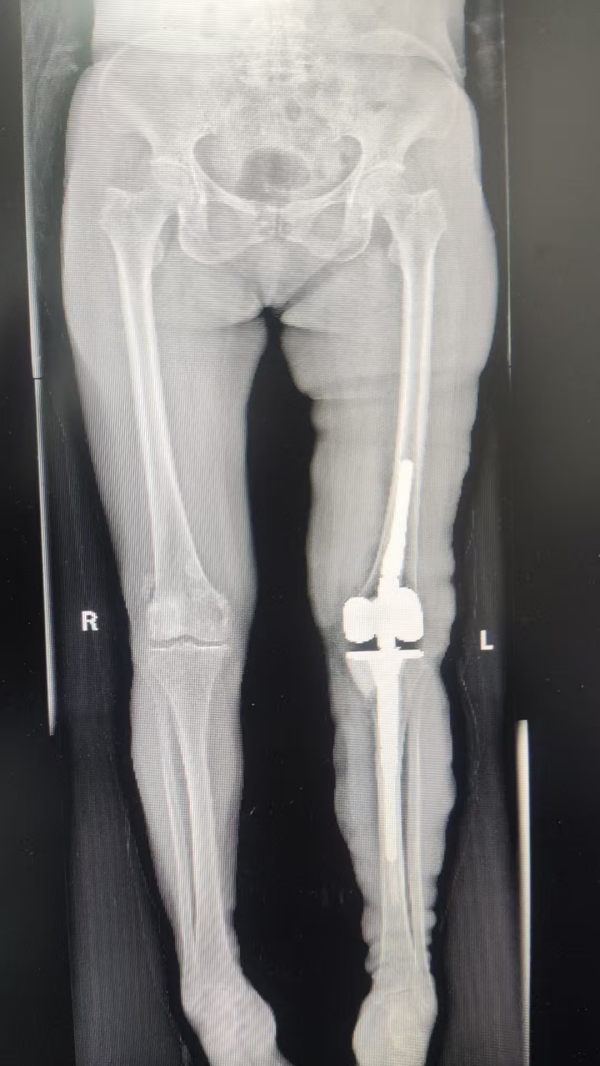

▲术后

术后,在医护团队的精心护理和科学康复指导下,患者恢复良好:膝关节疼痛显著缓解,活动功能稳步恢复。通过定期复查和康复方案调整,其关节功能持续改善,生活质量大幅提升。目前患者康复进程顺利,对治疗效果深感满意,并向医疗团队表达了由衷感谢。